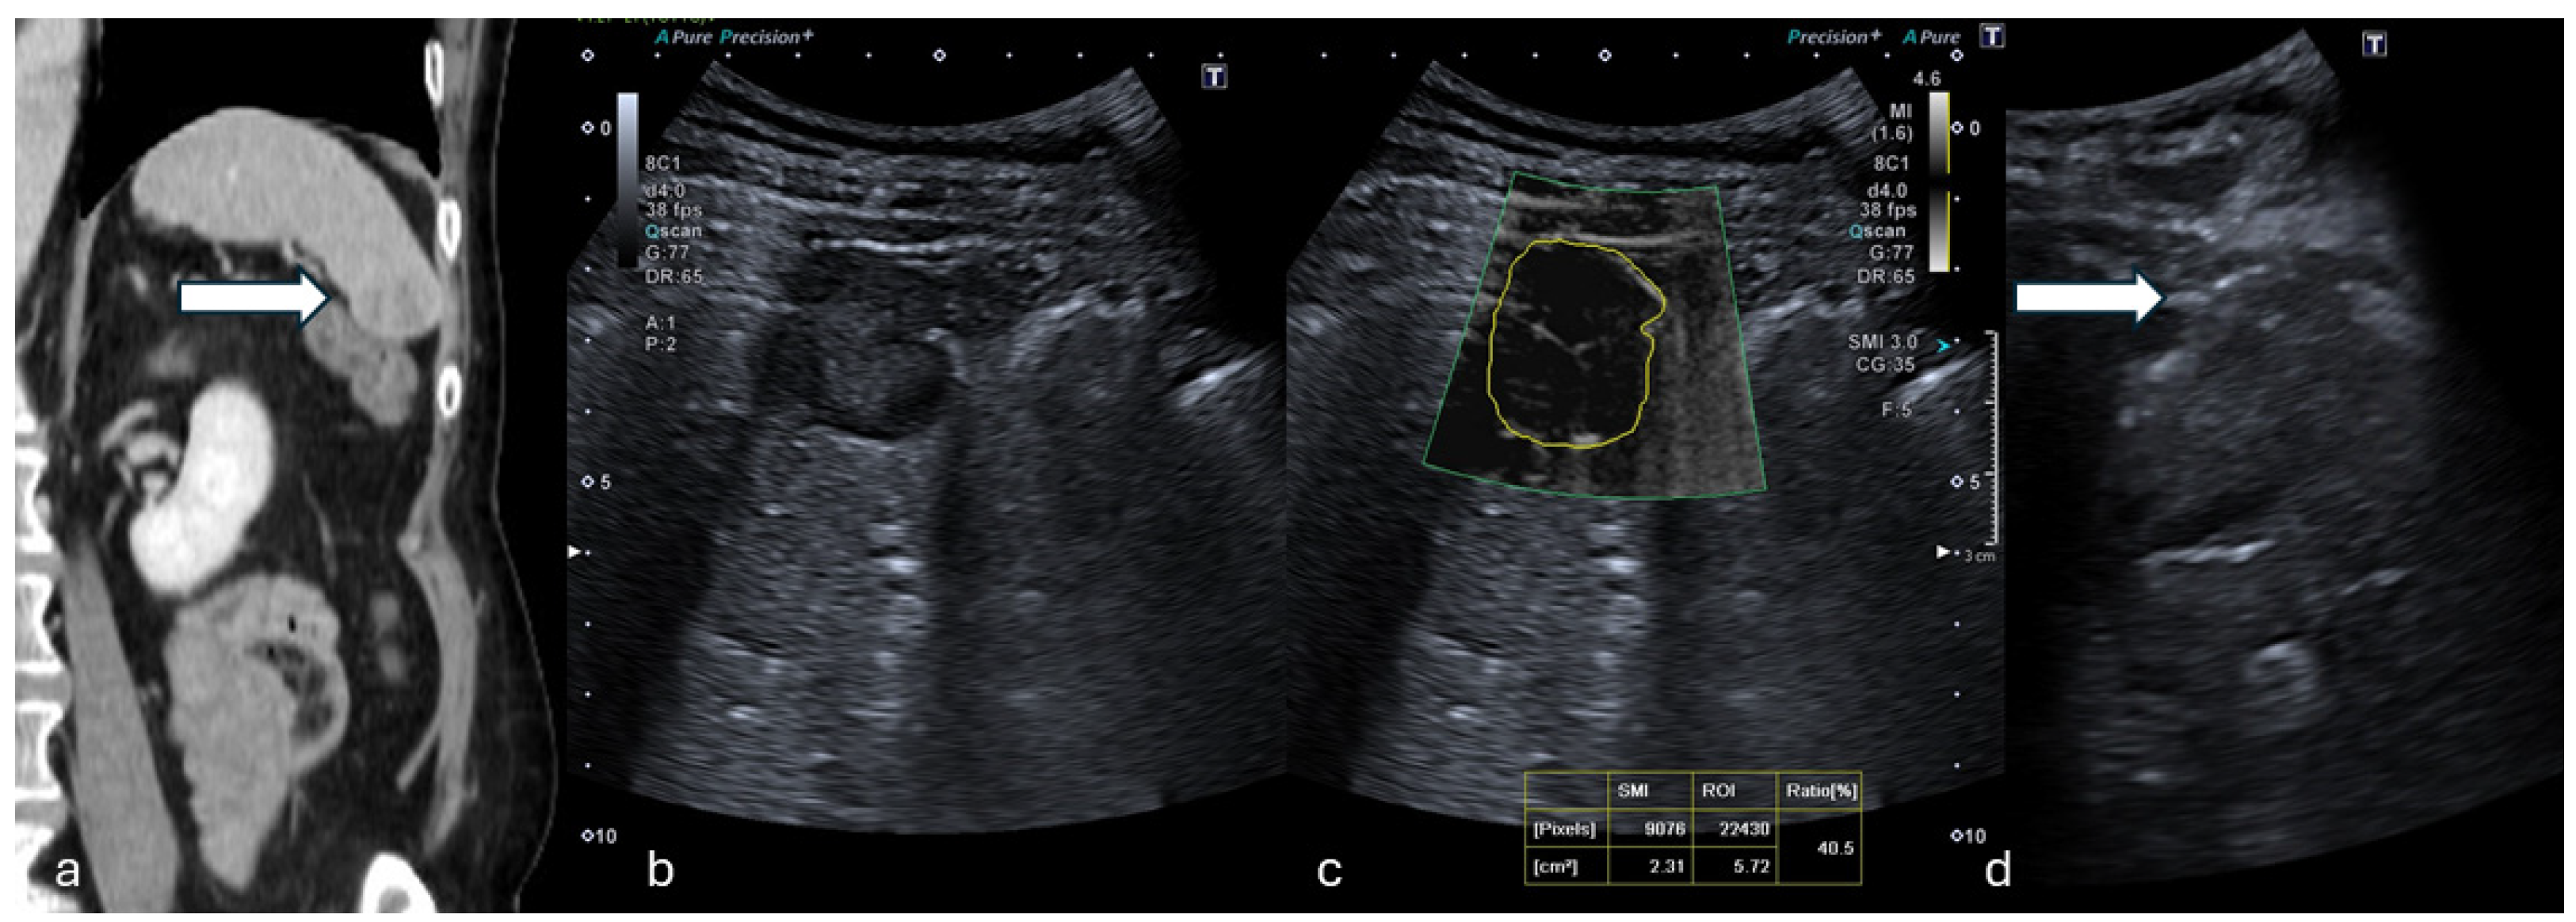

Figure 1.

(a) Coronal CT reconstruction in venous phase shows a hypodense 16 mm solid nodule of the spleen (white arrow). (b) B-mode US showed a dishomogeneous hypoechoic focal lesion with halo sign. (c) At mSMI, peripheral and central globular vessels were appreciable, VI measuring 40.5%. (d) Percutaneous biopsy using an 18G needle (white arrow). (Histological examination reported a lung cancer metastasis.).